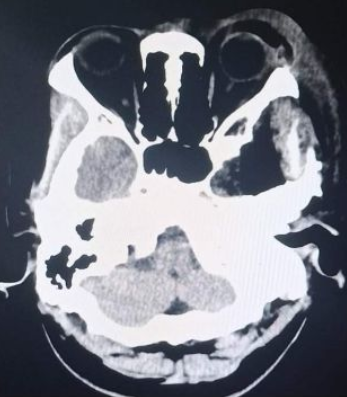

颅脑核磁示:左侧颞下窝占位。

术前核磁

术前增强MRI